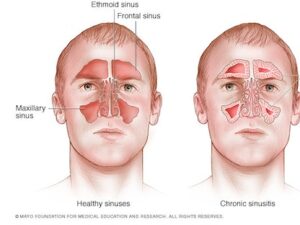

لأورام الأنفية والمجاورة للأنف هي زوائد تنمو في الممر داخل الأنف وحوله. تبدأ الأورام الأنفية في الممر الرئيسي داخل الأنف، ويُسمى تجويف الأنف. تبدأ الأورام